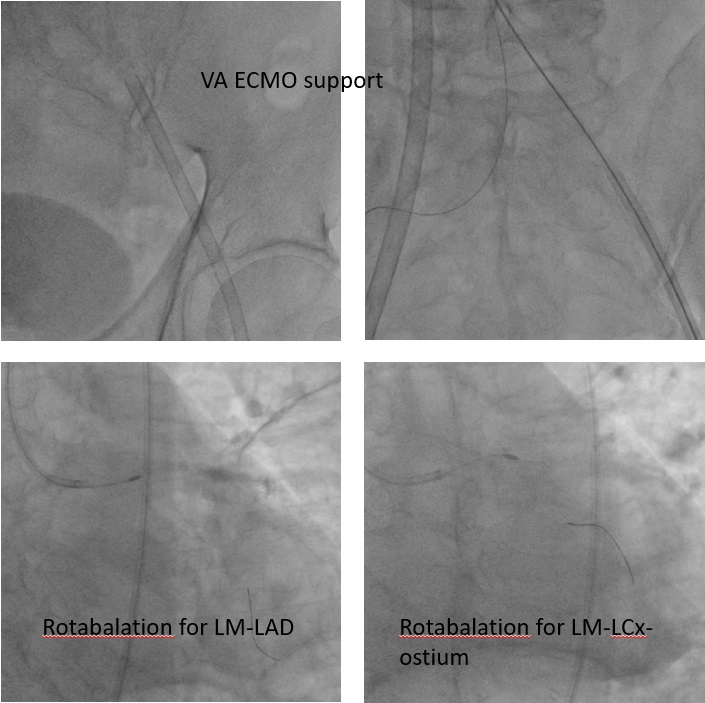

PCI was performed via a right femoral 7 Fr EBU 3.0 guide. LCX wiring was extremely challenging due to a large ostial aneurysm and discrete stenosis; reverse wiring failed, so the LAD was treated first. Using a Caravel microcatheter, an extra-support Rotawire was advanced, and sequential 1.25 mm and 1.75 mm burr atherectomy was done for LAD and LM–LAD segments. A 2.0 mm burr was avoided due to iliac angulation. After adequate LAD preparation, LCX wiring succeeded with a Suoh 03 wire, exchanged for a Rota Extra Support wire via Caravel. LM–LCX ostium was ablated with 1.25 and 1.75 mm burrs, though the burr could not enter LCX proper.